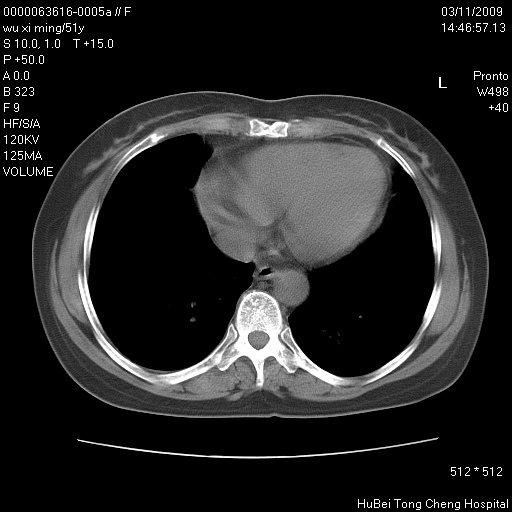

患者 女,51岁。因“胆囊炎,胆囊结石”,行常规术前胸部x线检查发现:右上肺结节病灶,建议行进一步检查。患者无咳嗽、咳痰及咯血等呼吸道症状,近期出现背部疼痛不适。

胸部ct轴位平扫(层厚10mm,螺距1.5,重建间隔10mm;部分层面:层厚3mm,螺距1.0,重建间隔3mm),图像如下:

右肺周围型肺癌伴肺内转移信胸椎转移

支持--右肺周围型肺癌---胸椎转移

支持右上肺肺癌并胸椎转移

右肺周围型肺癌伴肺内转移及胸椎转移。已无手术机会。